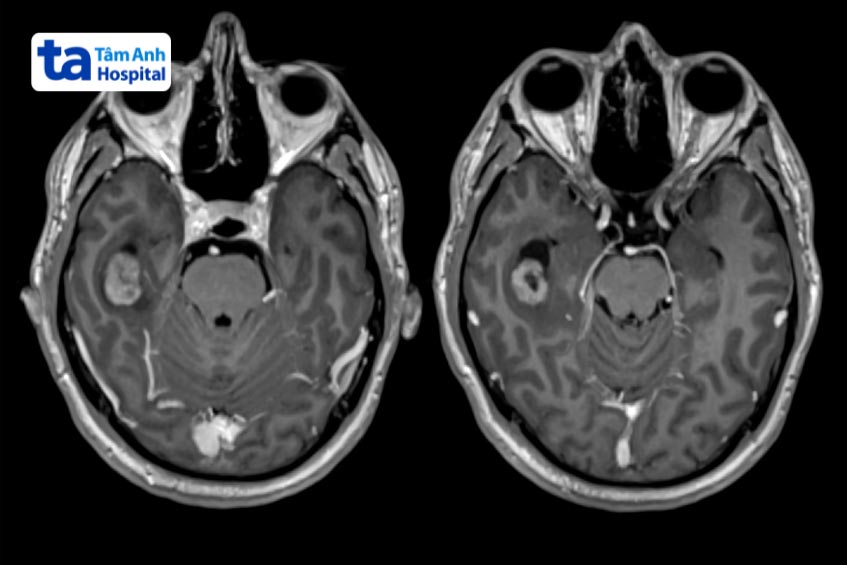

U góc cầu tiểu não (Cerebellopontine angle (CPA) tumors) là khối u lành tính, nằm ngoài trục, mọc lên trong khoang dịch não tủy, được giới hạn bởi cầu não, bán cầu tiểu não và đỉnh xương đá.

Theo thống kê của The National Center for Biotechnology Information Hoa Kỳ, u vùng góc cầu tiểu não chiếm khoảng 5-10% tổng số khối u nội sọ. Trong đó, 70‑85 % là u dây thần kinh tiền đình (dây VIII), 10‑15 % là u màng não. Bệnh thường gặp ở người từ 35 đến 40 tuổi. Phẫu thuật điều trị khối u thường gặp nhiều khó khăn, do không gian hẹp và khối u bám dính vào các cấu trúc thần kinh, mạch máu quan trọng. (1)

Để chẩn đoán u ở góc cầu tiểu não, bác sĩ có thể chỉ định thực hiện các xét nghiệm chuyên sâu, gồm: